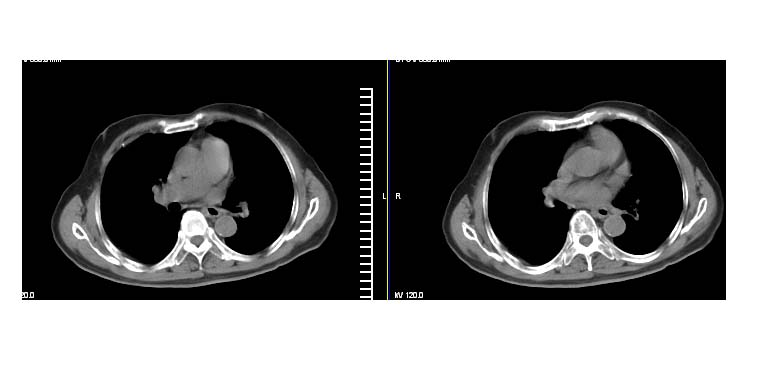

标题: CT11087:男性,82.咳嗽一周.抗炎治疗4-5天效果不明 [打印本页]

标题: CT11087:男性,82.咳嗽一周.抗炎治疗4-5天效果不明

左上肺周围型肺癌伴纵隔淋巴结转移

考虑左上肺周围型肺癌伴纵隔淋巴结转移。

左上肺软组织肿块,有分叶,短毛刺,气管旁间隙见有肿大淋巴结,考虑左上周围型肺癌伴纵隔淋巴结转移。